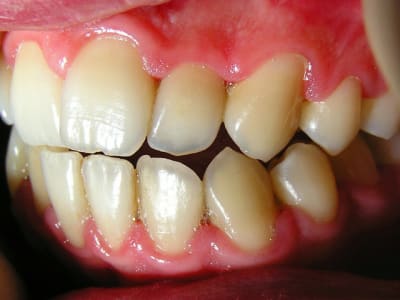

J'ai revu mon gendarme ce soir après 9 jours de flagyl + brosse Inava 15/100 trempée dans le paroex.

Il va beaucoup mieux: plus de douleurs bien sûr, presque pas de saignements, halitose disparue...

J'ai ressorti les photos prises initialement:

...Et les photos prises aujourd'hui, juste avant la séance de démonstration du contrôle de plaque.

Le but est de le revoir dans un mois pour déterminer sa motivation et son efficacité en matière de contrôle de plaque. Et pour voir comment la flore recolonise le terrain avant de lithotritier.